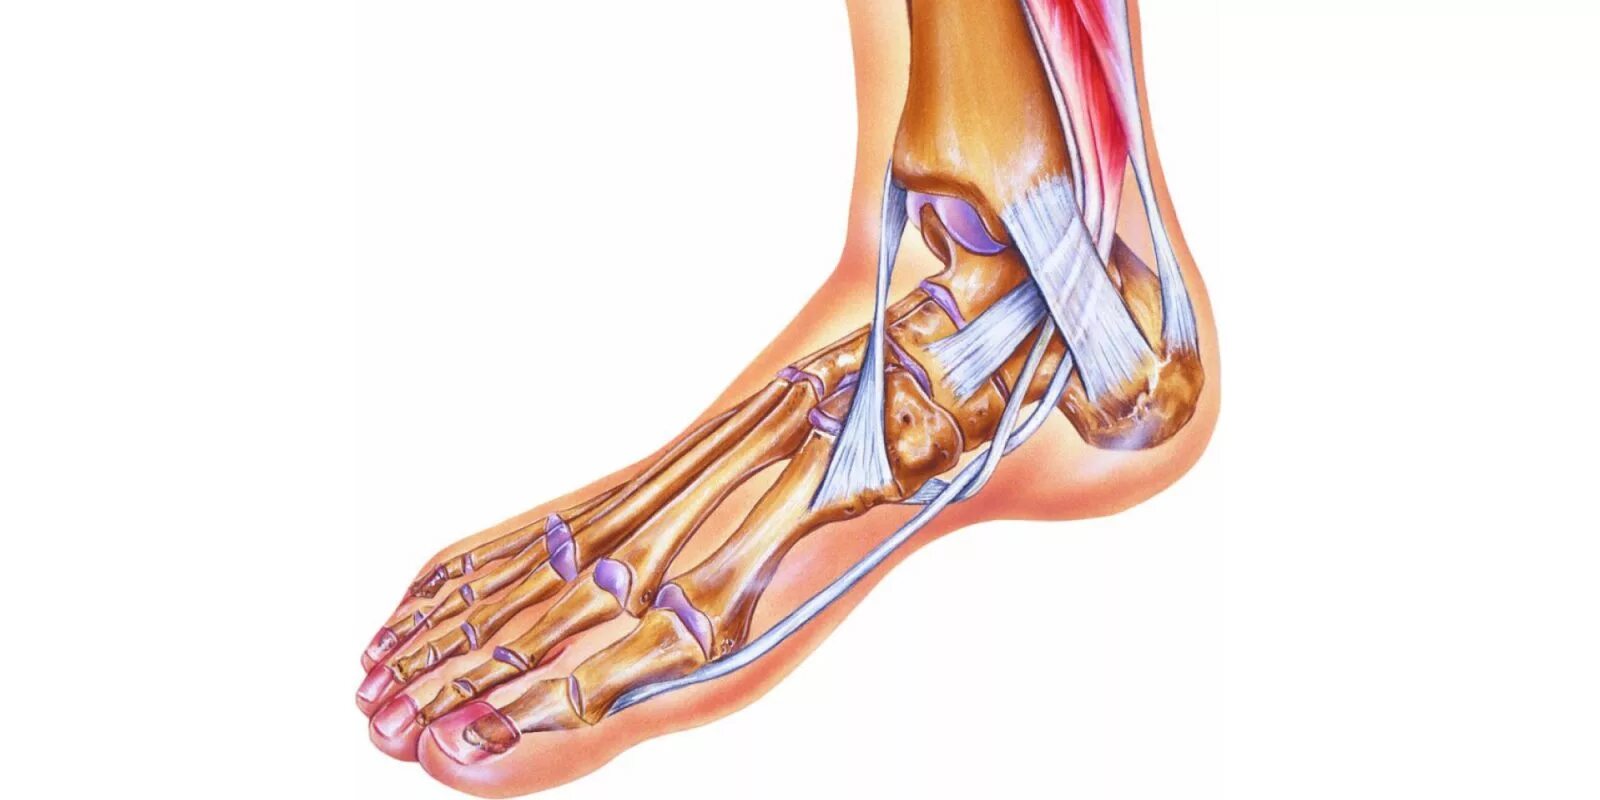

Вывих растяжение ноги